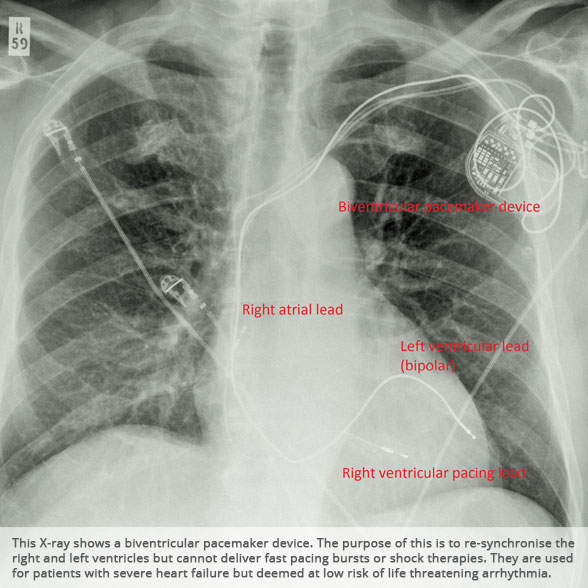

Biventricular pacemaker device Biventricular pacemaker device

Above: Slideshow containing X-rays of common medical procedures.

BI-VENTRICULAR PACEMAKERS

Bi-ventricular pacemakers are used for the treatment of suitable patients with heart failure who are already on medication but who suffer from a lack of synchrony between the right and left ventricular contraction. This is most commonly caused by an electrical delay (left bundle branch block LBBB) in transmission of signals to the main pumping chamber (called the left ventricle) and is relatively common in patients with advanced heart failure. This delay process commonly worsens the symptoms of heart failure and it is not generally influenced by medication alone.

Although not all patients universally respond to bi-ventricular pacing (or cardiac resynchronisation therapy/CRT), patients with more advanced dys-synchrony tend to experience remarkable improvement. Bi-ventricular ICDs have the additional benefit of recognising life threatening arrhythmia and deliver both fast pacing bursts or shocks to restore normal heart rhythm.